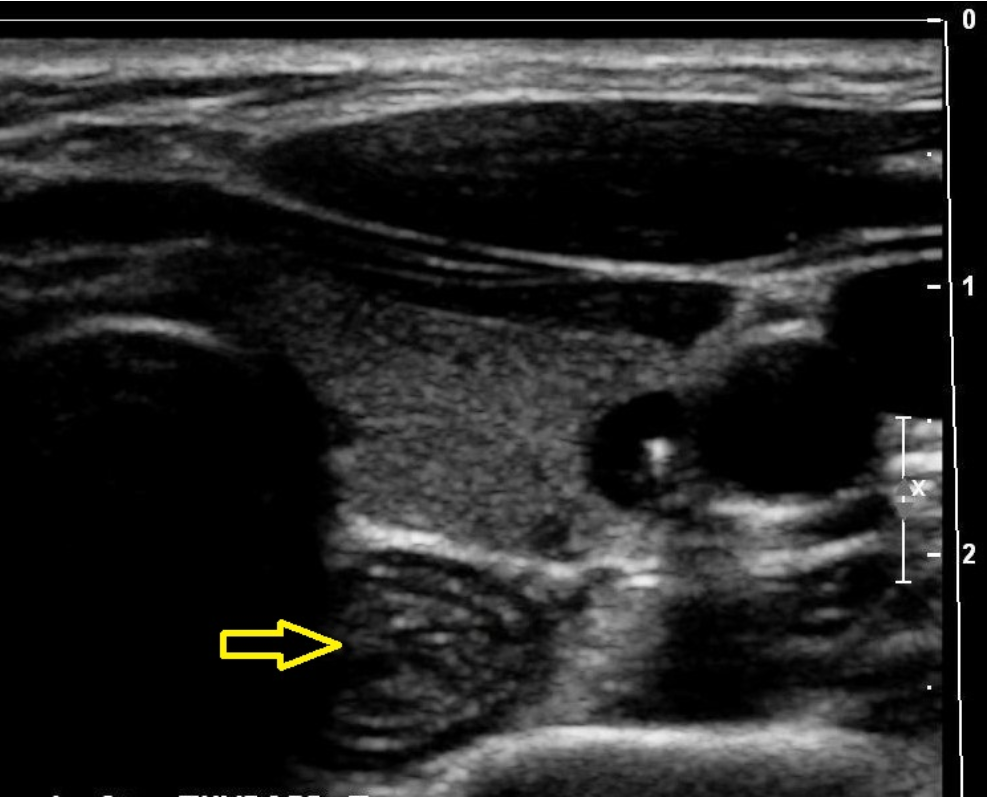

What is indicated by the yellow arrow?

C. esophagus

The arrow indicates the esophagus. Note the rings of tissue seen with normal Gl tract structures.